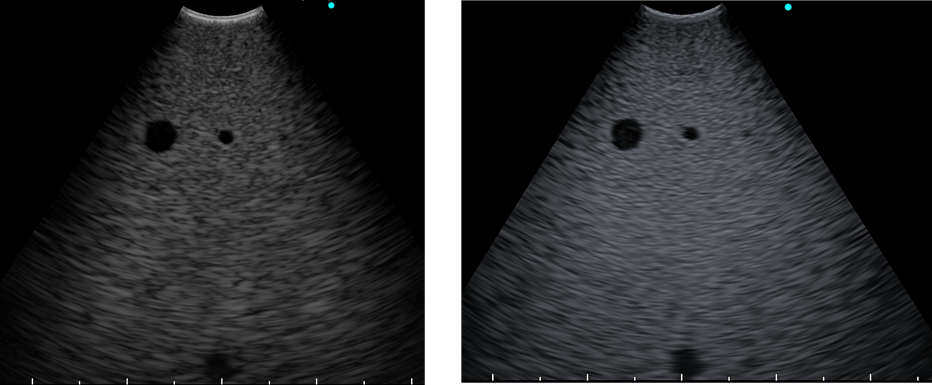

使用 B 模式或更高階的THE模式生成超音波影像

B 模式

與EU-ME2相比,解析度和穿透深度均有所提升。

以下為兩款機型分別連接 BF-UC290F 的畫面。

THE 模式

利用高諧波提升影像解析度,減少偽影(Artifacts),以精準診斷膽囊、膽管。